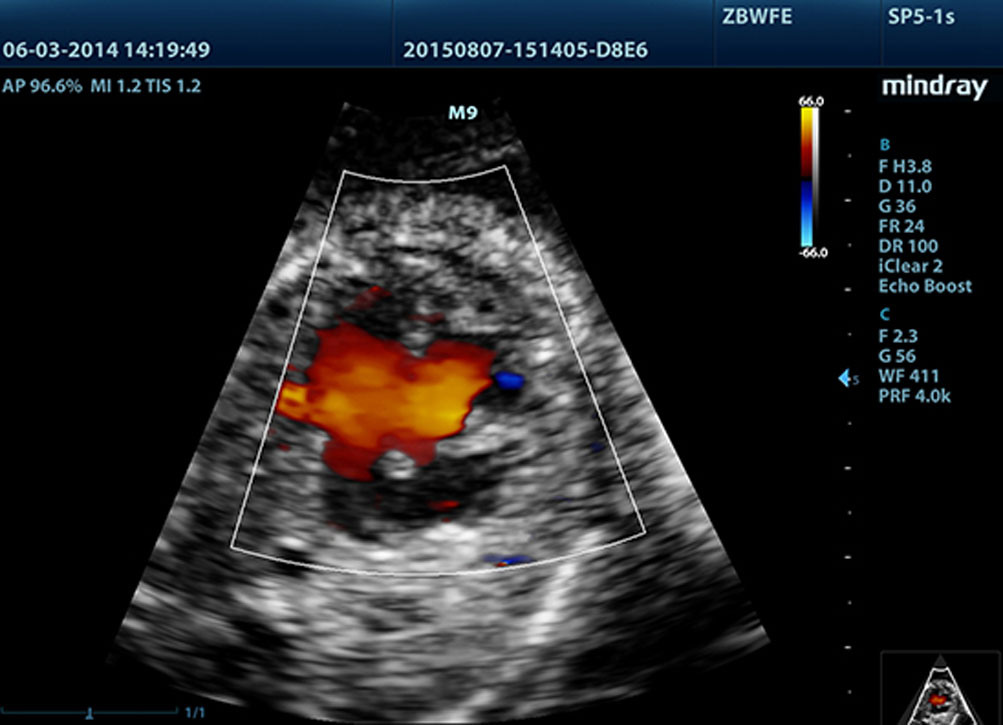

Fornendo immagini pi├╣ nitide, tutte le sonde compatibili con M9 sono dotate della tecnologia Mindray tecnologia trasduttore 3T, unica nel suo genere. Migliorato con l'aggiunta della tecnologia monocristallo, M9 offre una migliore penetrazione e un flusso dinamico del colore, in particolare durante la scansione di pazienti difficili.

La tecnologia Mindray di elaborazione adattativa del segnale con rilevamento dell'eco intelligente, unica nel suo genere, progettata per utilizzare le informazioni native segnale-rumore per migliorare i segnali eco deboli, mentre sopprime i disturbi del rumore circostante, fornendo una pi├╣ equilibrata luminosit├Ā dellŌĆÖimmagine ed una migliore visone degli strati di tessuto miocardico.

LVO per ecocardiografia sotto stress

Le eccezionali capacit├Ā di M9 consentono lŌĆÖopacizzazione LV durante lo stress, migliorando distinzione tra tessuto miocardico e ristagno di sangue, fornendo una migliore visualizzazione della superficie endocardica. La funzione Stress Echo di M9 comprende un pacchetto completo per lo stress farmacologico e da sforzo. Il pacchetto ├© supportato da un sistema flessibile di rapporto che pu├▓ essere ottimizzato sulle esigenze individuali.